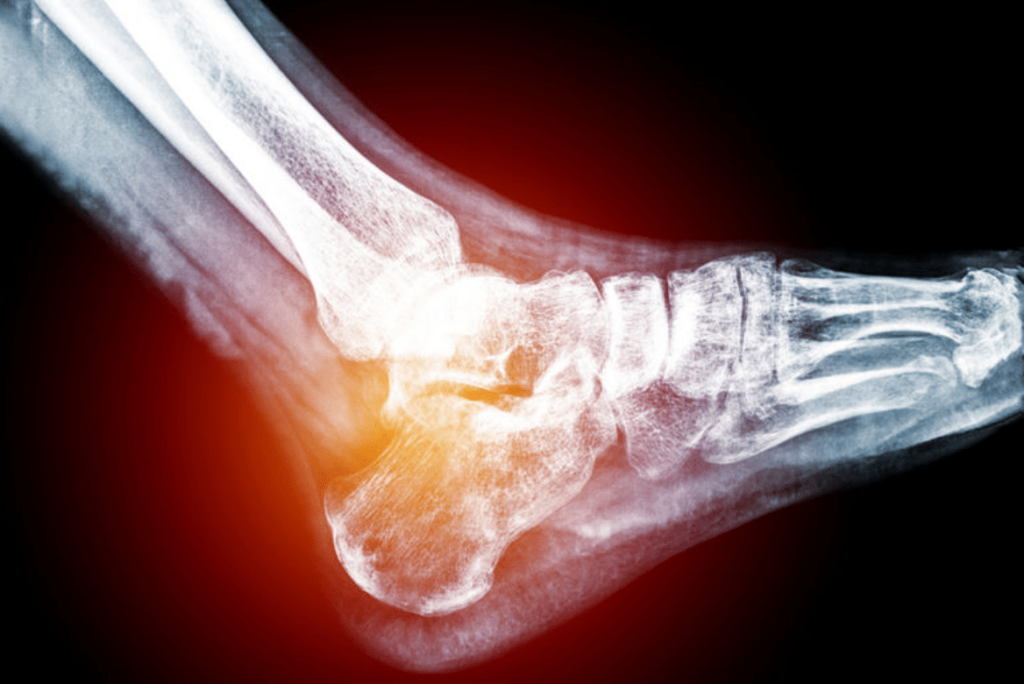

Our daily lives require us to move effectively from one place to another, so when your mobility is limited due to an ankle injury or foot pain, it can have a negative impact on your quality of life. Each foot contains 28 bones, 30 joints and more than 100 muscles, tendons and ligaments. Without all the parts working optimally, the result can be foot pain and diminished ability to stand, walk and run. Fortunately, if you’re experiencing foot pain, help is available.

Feet are complex anatomical structures, all-in-one stabilizers, shock absorbers, and propulsion engines that are instrumental to overall health and well-being. They require expert care. Be sure you’re seeing the most qualified health-care professional to treat your feet by looking for the letters “DPM” after his or her name. The DPM means a physician has completed years of rigorous foot and ankle training in podiatric medical school and hospital-based residency training, making him or her uniquely qualified to care for this part of the body.